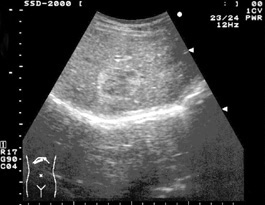

・肝血管腫:マージナルストロングエコー

肝血管腫で辺縁にほぼ全周性に縁取られるように見られる高エコー(高輝度)所見のことを指します。